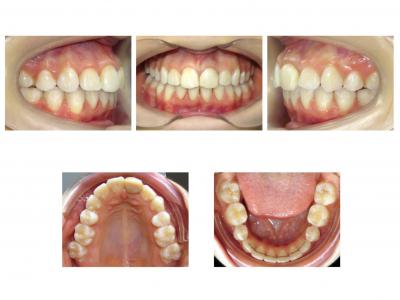

Voici les deux patientes traitées

Ici, dans les deux cas, les deuxièmes prémolaires ont été extraites et les traitements ont duré 18 mois.

Dans le premier cas, la béance s'est fermée spontanément (pas prévu au départ) sans rééducation, sans appareil de contrainte linguale, ni élastique. Il semblerait que le gain de place a permis aux incisives de se redresser spontanément et donc de fermer la béance. La fermeture de la béance, la normalisation de l'environnement anatomique a permis à la langue de se mettre à travailler correctement. Pour le sens transversal, la correction a été aussi spontanée. Juste une minivis dans le secteur 1 a été placée pour recentrer mon milieu (ancrage maximal recherché au départ). Les finitions auraient pu être meilleures. Elle finit avec une légère classe II (on va dire qu’elle est surcorrigée :)). Le traitement a terminé plus tôt que prévu (24 mois annoncé), car problèmes de santé.

NB : totalement stable à 1 an